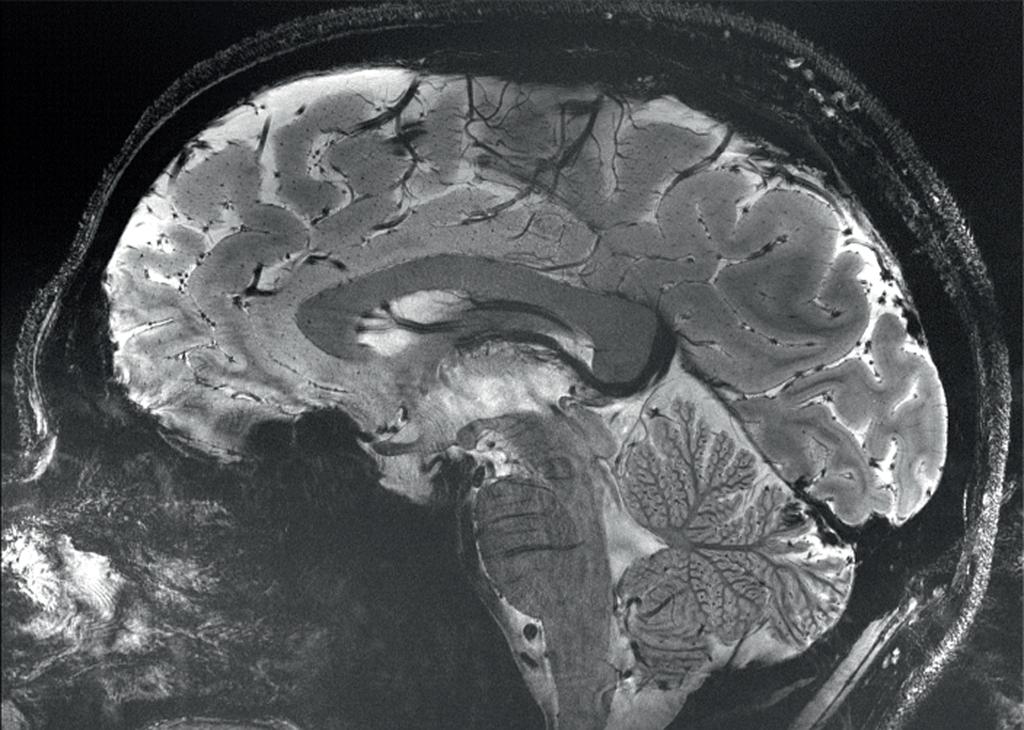

• 分析了近11,000人的大腦核磁共振圖像